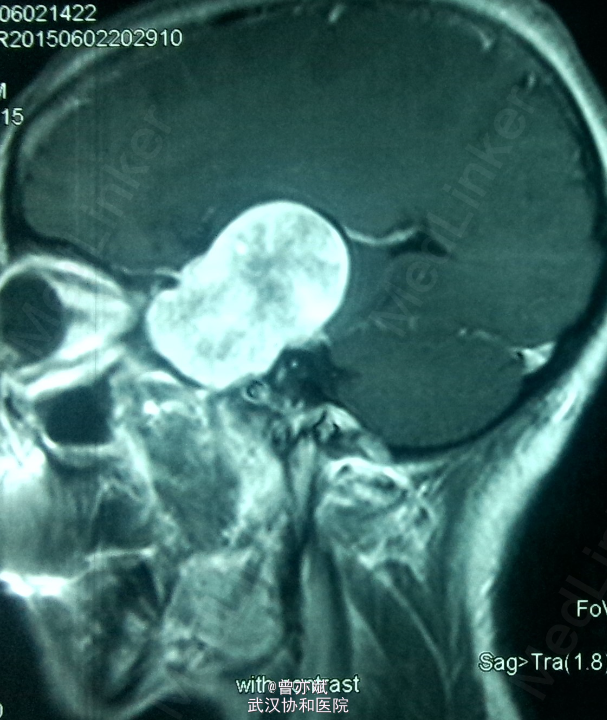

查体:左眼视力0.8 颞侧偏盲,右眼视力 0.5 余无明显阳性体征。既往无特殊。 MRI: 稍长 T1,高flair信号,增强明显强化 ,其内点片状强化减低区。诊断:鞍区、中颅窝底巨大占位,考虑脑膜瘤可能性大。

诊断:脑膜瘤?海绵状血管瘤? 处理:手术切除 。

从 MRI上看,矢状位 增强可疑脑膜尾征,增强虽然明显但 不均匀 ,酷似脑膜瘤表现,手术中所见血供丰富,肿瘤实质多为血窦,考虑海绵状血管瘤。如果术前 能 诊断是海绵状血管瘤 ,是开颅手术还是分次伽马刀? 有大神指点一二不?